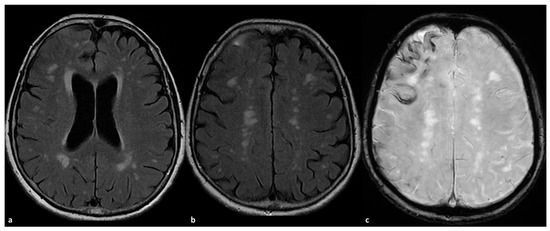

Some examples of the association of SDH with CAA and CAA-related inflammation are proposed in Figure 1 and Figure 2.

Figure 2. CAA-related inflammation with prominent sulcal effacement and gyral swelling in the right frontal pole ((a,b), axial FLAIR) with simultaneous pachymeningeal involvement and small satellite subdural collection (a,b). The patient has a diffuse cSS ((c) SWI) with clustering on the right frontal pole.